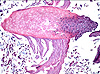

CASO N° 4 (Dr. Bonan e Dr. Roman)

Paciente do gênero masculino, 46 anos de idade, apresenta lesão no palato.